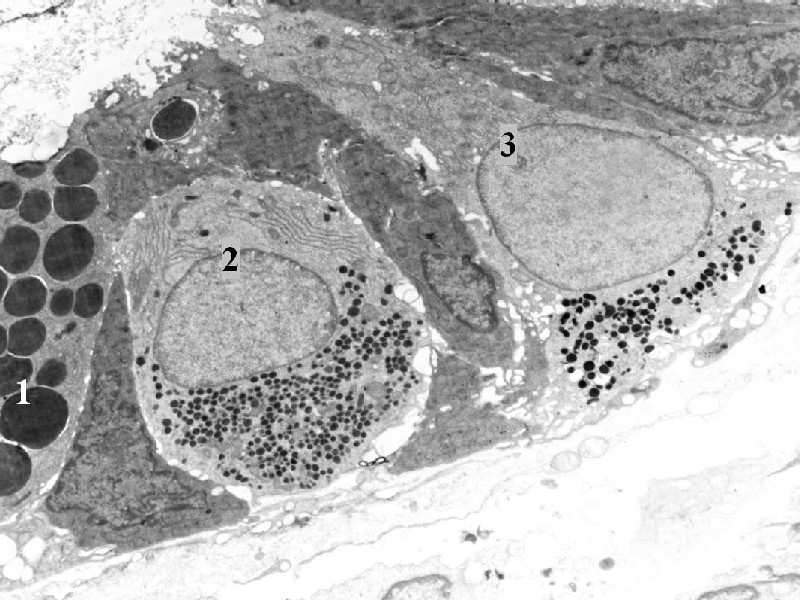

Enteroendokrinní buňky ve střevní kryptě - v blízkosti je Panethova buňka (1) - uzavřený (2) a otevřený (3) typ

endokrinní buňky.